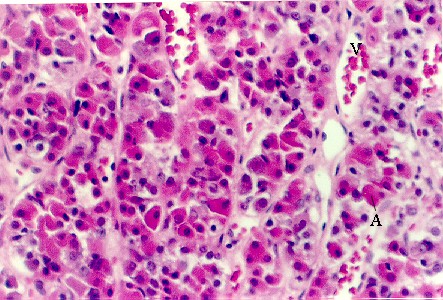

The above photos show  higher magnifications of the pars distalis.   You should be able to distinguish acidophils and basophils in this and your slide.   To do this, look at the color of the red blood cells in the vessels (V).   Then, match the color to cells in the pituitary.  Those are the acidophils (A).  Cells that are more "purple", or blue are the basophils (B).   Cells that have hardly any color are the chromophobes.  There are few true chromophobes since at the electron microscopic level most pituitary cells have the granules that are characteristic of a particular cell type.  They are simply degranulated acidophils or basophils.

If you saw a pituitary with a large mass of acidophils (adenoma), what hormones might be produced by this tumor?____________________________________?

In hypothyroid individuals, certain types of basophils enlarge and become vacuolated. What is causing this response______________________________? Which basophils are responding?___________________________

What is the probable function of most chromophobes_________________?